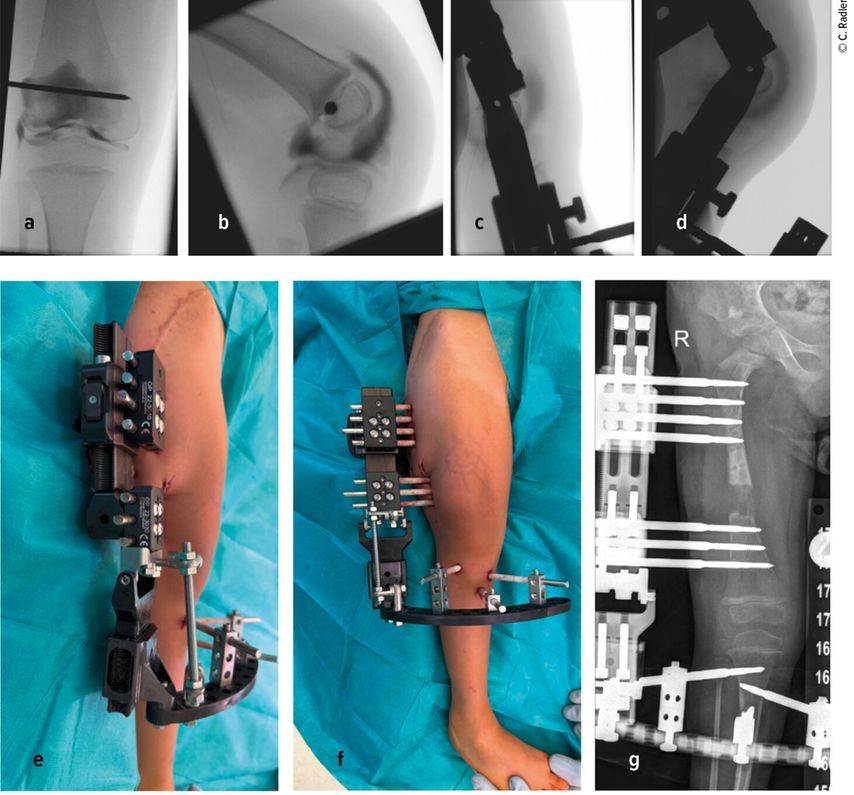

Die Valgusstellung kann sehr einfach über eine Wachstumslenkung (Hemiepiphysiodese mit 2-Loch-Platte) korrigiert werden. Um eine Subluxation am Kniegelenk zu verhindern, muss bei allen diesen Fällen bei Verlängerung mit Fixateur dieser knieüberbrückend montiert werden (Abb.4). Bei Verlängerung über einen Verlängerungsmarknagel wird in diesen Fällen eine Oberunterschenkelschiene (KAFO) verwendet und prophylaktisch, soweit noch vorhanden, die Fascia lata auf Höhe des oberen Patellapols durchtrennt. Bei deutlicher Instabilität oder auch Subluxation ist eine Stabilisierung über eine komplexe Operation, die als Super-Knee-Operation subsumiert wird, erforderlich.2 Diese Operation kann auch an die Hüftrekonstruktion/Super-Hip-Operation angeschlossen werden, da hier die Faszie ohnehin präpariert wird. Je nach Alter des Patienten und dem Ausmaß der Instabilität wird hierbei die Fascia lata nach Präparation bis an das Tuberculum Gerdyi und Halbieren der Länge nach entweder extraartikulär oder intraartikulär geführt. Auch die Fixation wird abhängig vom Alter mit Biotenodeseschrauben oder Weichteilzügelung durchgeführt.

Abb. 4: Platzierung (a–d) eines Fixateur externe mit Knie-Überbau (e–g) zum Schutz vor (Sub-)Luxation